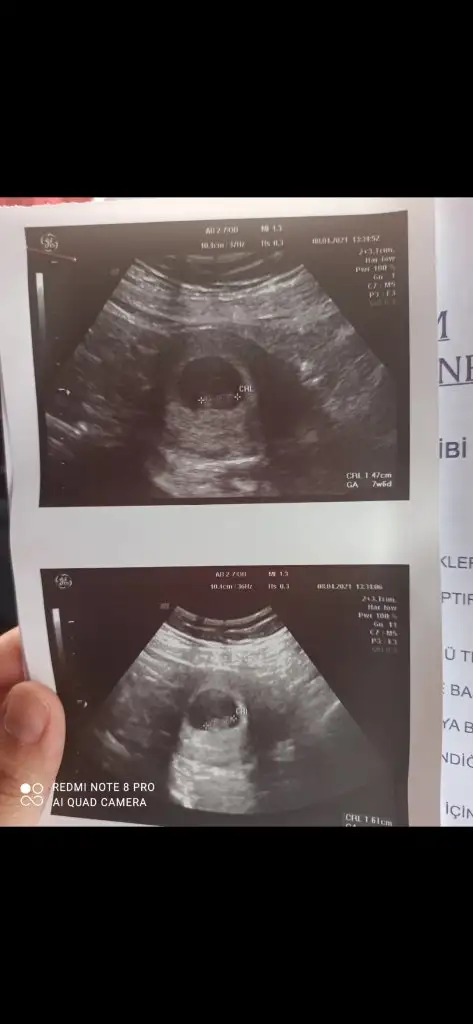

Kız olabilir en iyi 11 12 13 haftalar olmalıBenimkini de tahmin edebilirsiniz8+3

Teşekkür ederimKız olabilir en iyi 11 12 13 haftalar olmalı